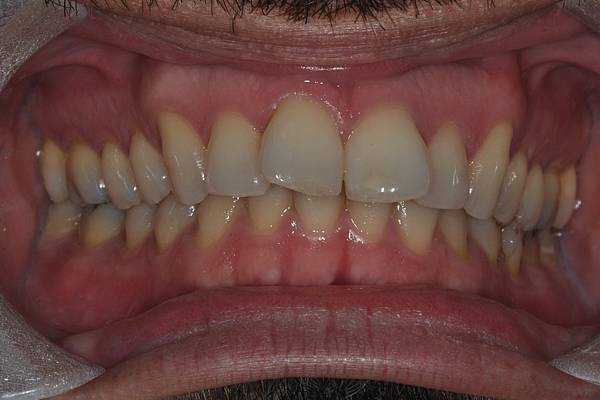

台灣的牙科醫療品質, 連外國人都說讚!此案例為深咬合併二級咬合 林醫師藉由正中上顎骨釘(HPPG technique)做上顎全齒列後移改善暴牙 讓本來五官就相當立體的艾先生,笑起來更燦爛了! 治療前/治療後-以上案例由林昇進醫師提供 分享到